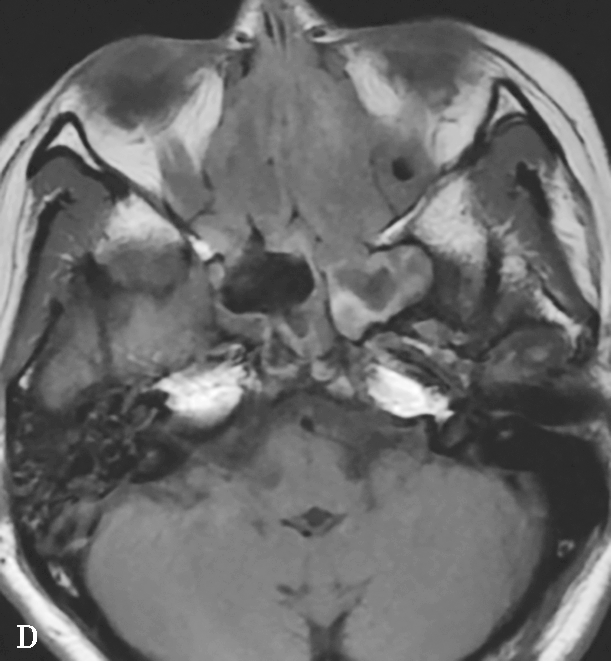

图1-3-23 急性侵袭性真菌性鼻窦炎

A、B.横断面、冠状面CT骨窗,示双侧蝶窦、后组筛窦软组织影,密度不均,窦壁骨质硬化伴局部骨质破坏,累及双侧圆孔、翼管;C~E.MRI横断面T 1 WI、T 2 WI、T 1 WI+FS+C,示双侧蝶窦、后组筛窦内混杂长T 1 、长T 2 信号,窦腔内见斑片状短T 1 、短T 2 信号影,增强扫描边缘强化,前颅底脑膜增厚强化